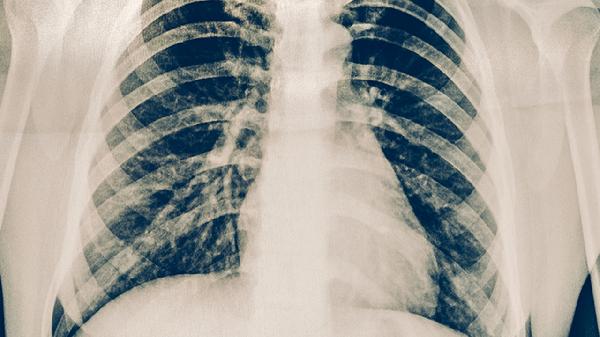

右侧胸下肋骨疼可通过热敷、调整姿势、服用非甾体抗炎药、局部封闭治疗、手术修复等方式缓解。右侧胸下肋骨疼可能与肋软骨炎、肋骨骨折、胆囊炎、胸膜炎、带状疱疹等因素有关。

严重肋骨骨折移位或合并血气胸时,可能需行肋骨内固定术或胸腔闭式引流术。术后需使用多头胸带固定6-8周,期间避免剧烈咳嗽。慢性胆囊炎反复发作者可考虑腹腔镜胆囊切除术。